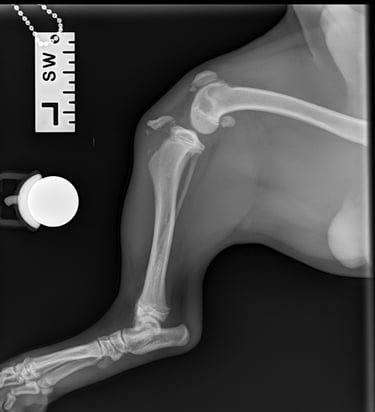

Lateral radiographs revealed a complete avulsion of the left tibial crest (Fig. 1), along with a mild lesion at the distal pole of the patella. For comparison, a lateral view of the right limb is included, demonstrating a normal appearance of the tibial crest growth plate (Fig. 2).

Fig. 1